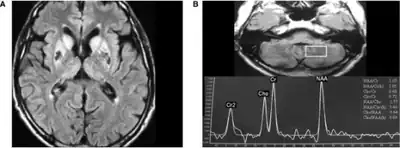

Neuroferritinopathy is most commonly diagnosed using MRI and other neuroimaging techniques.[1] MRIs help identify the iron deposits in the cerebellum, basal ganglia, and motor cortex common to neuroferritinopathy.[8] MRIs of affected individuals also show mild cerebellar and cerebral atrophy, or tissue breakdown, and gas cavity formation in the putamen.[8] Most importantly, the MRIs show misfolded ferritin proteins and iron deposits in the glial cells of the caudate, putamen, globus pallidus, cerebral cortex, thalamus, and purkinje cells, causing neuronal death in these areas.[8]

-

a)High signal caudate and lenticular nuclei b) long echo time in deep left cerebellum -

MRI